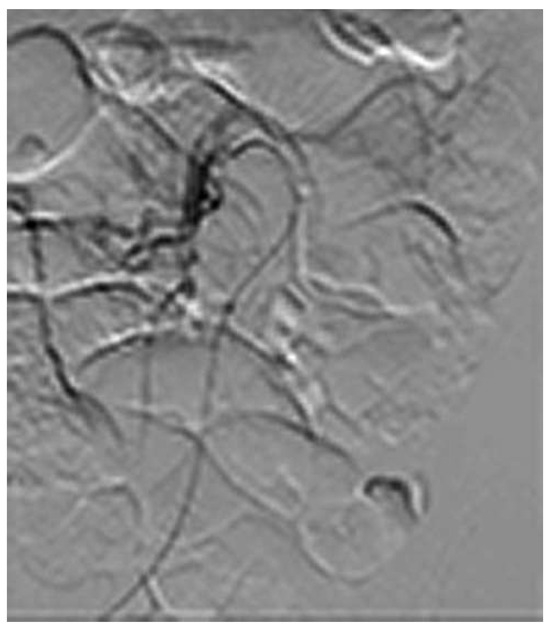

Cardiac Contractility Modulation for Treatment of Heart Failure

by Haran Burri and Pierre Bordachar

Abstract

Cardiac contractility modulation has been studied for over a decade to treat heart failure. This article provided an overview of the suggested mechanisms of action and current evidence of efficacy, and discusses the clinical perspectives of this therapy. Full article